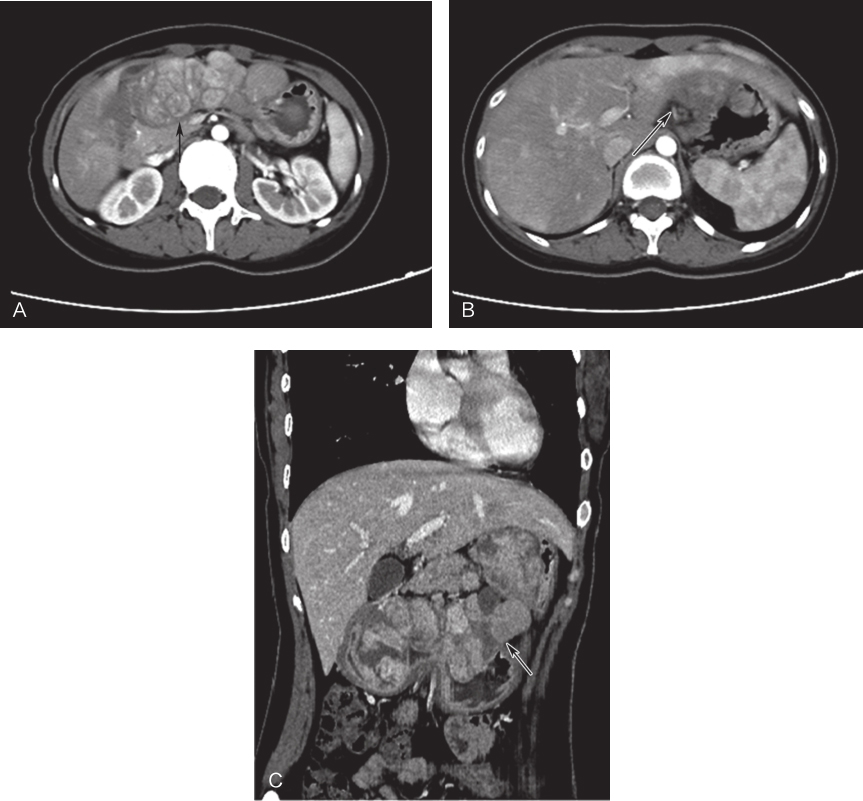

患者,女性,24岁,于2015年9月因“呕血3小时、便血3天”就诊于当地医院。行腹部CT示:①胃多发高密度影肿块,考虑肿瘤性病变,胃GIST?②肝脏多发低密度影,肝内血管瘤可能(图1)。胃镜示:胃体-胃角-胃窦可见数个大小不一的球形及半球形隆起,呈串珠样排列,胃窦处最大一个约为7.0cm×7.0cm,表面糜烂。穿刺活检示:镜下可见数小团梭形细胞;免疫组织化学染色示:CD117(+),CD34(+),DOG-1(+),SMA(-);因组织量较少未行基因检测。结合免疫组织化学染色及临床病史,符合(胃)胃肠间质瘤,当地医院给予口服伊马替尼治疗,400mg/d。

图1首诊CT

A、B.横断位;C.冠状位